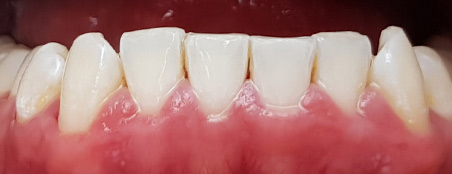

Наши работы

Перед началом лечения делаются цифровые фотоснимки полости рта. Эти съемки регулярно повторяются, чтобы фиксировать изменения в положении зубов. Еще один способ оценить масштаб проблемы – изготовить гипсовые модели челюстей, чтобы пациент мог убедиться в изменении положения зубов и общей запущенности болезни. Кроме того, на такой модели врачу удобнее проводить все необходимые измерения.